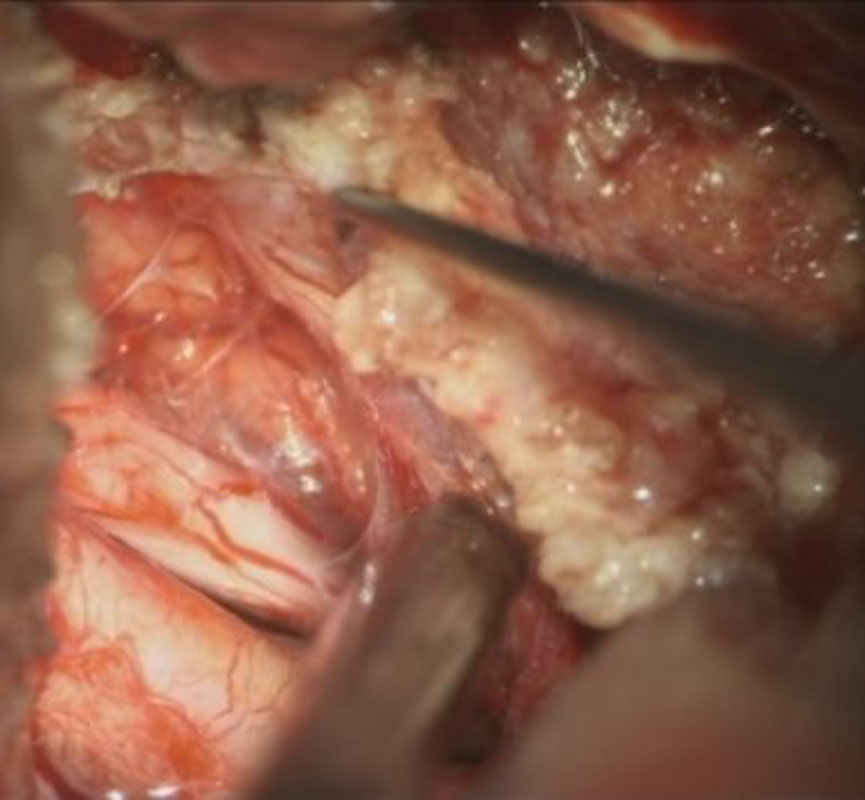

No.’25_88 摘出 前

No.’25_88  摘出 中